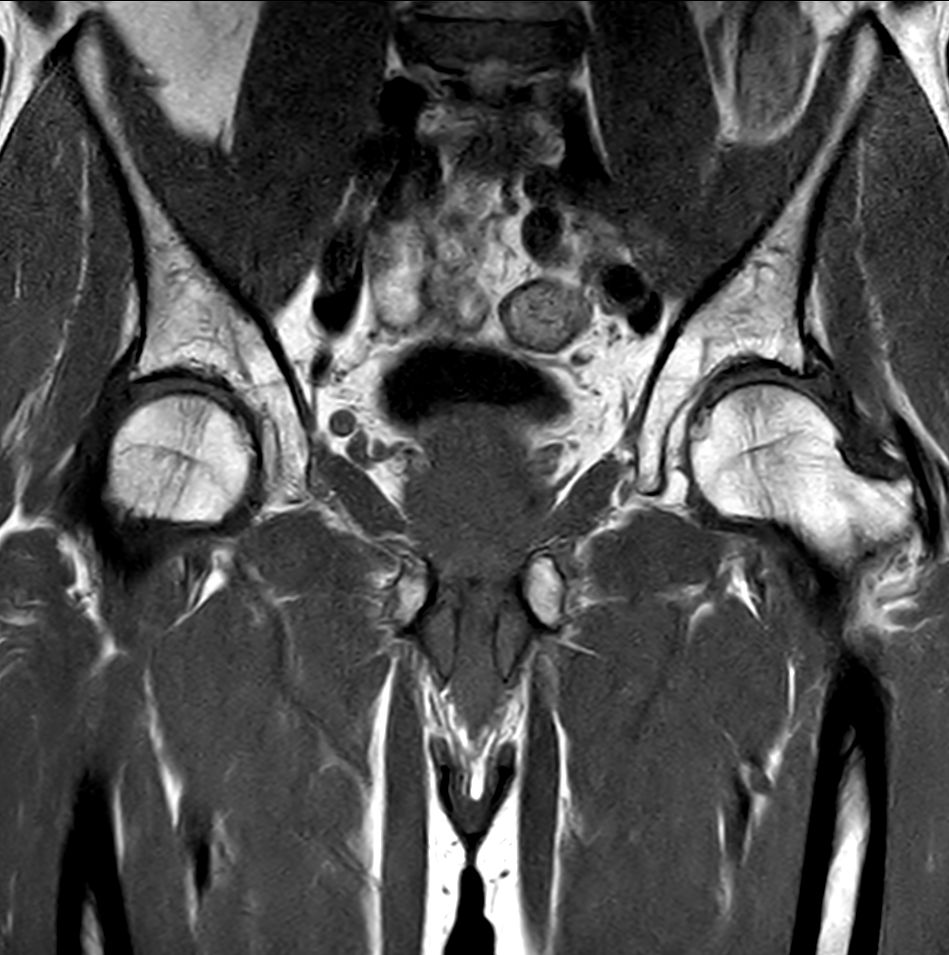

For prostate exams, the MSK M coil can be used in combination with the posterior coil, delivering exceptional quality MR images and high patient satisfaction.

Premium signal-to-noise ratio is achieved via dStream, providing outstanding image resolution.